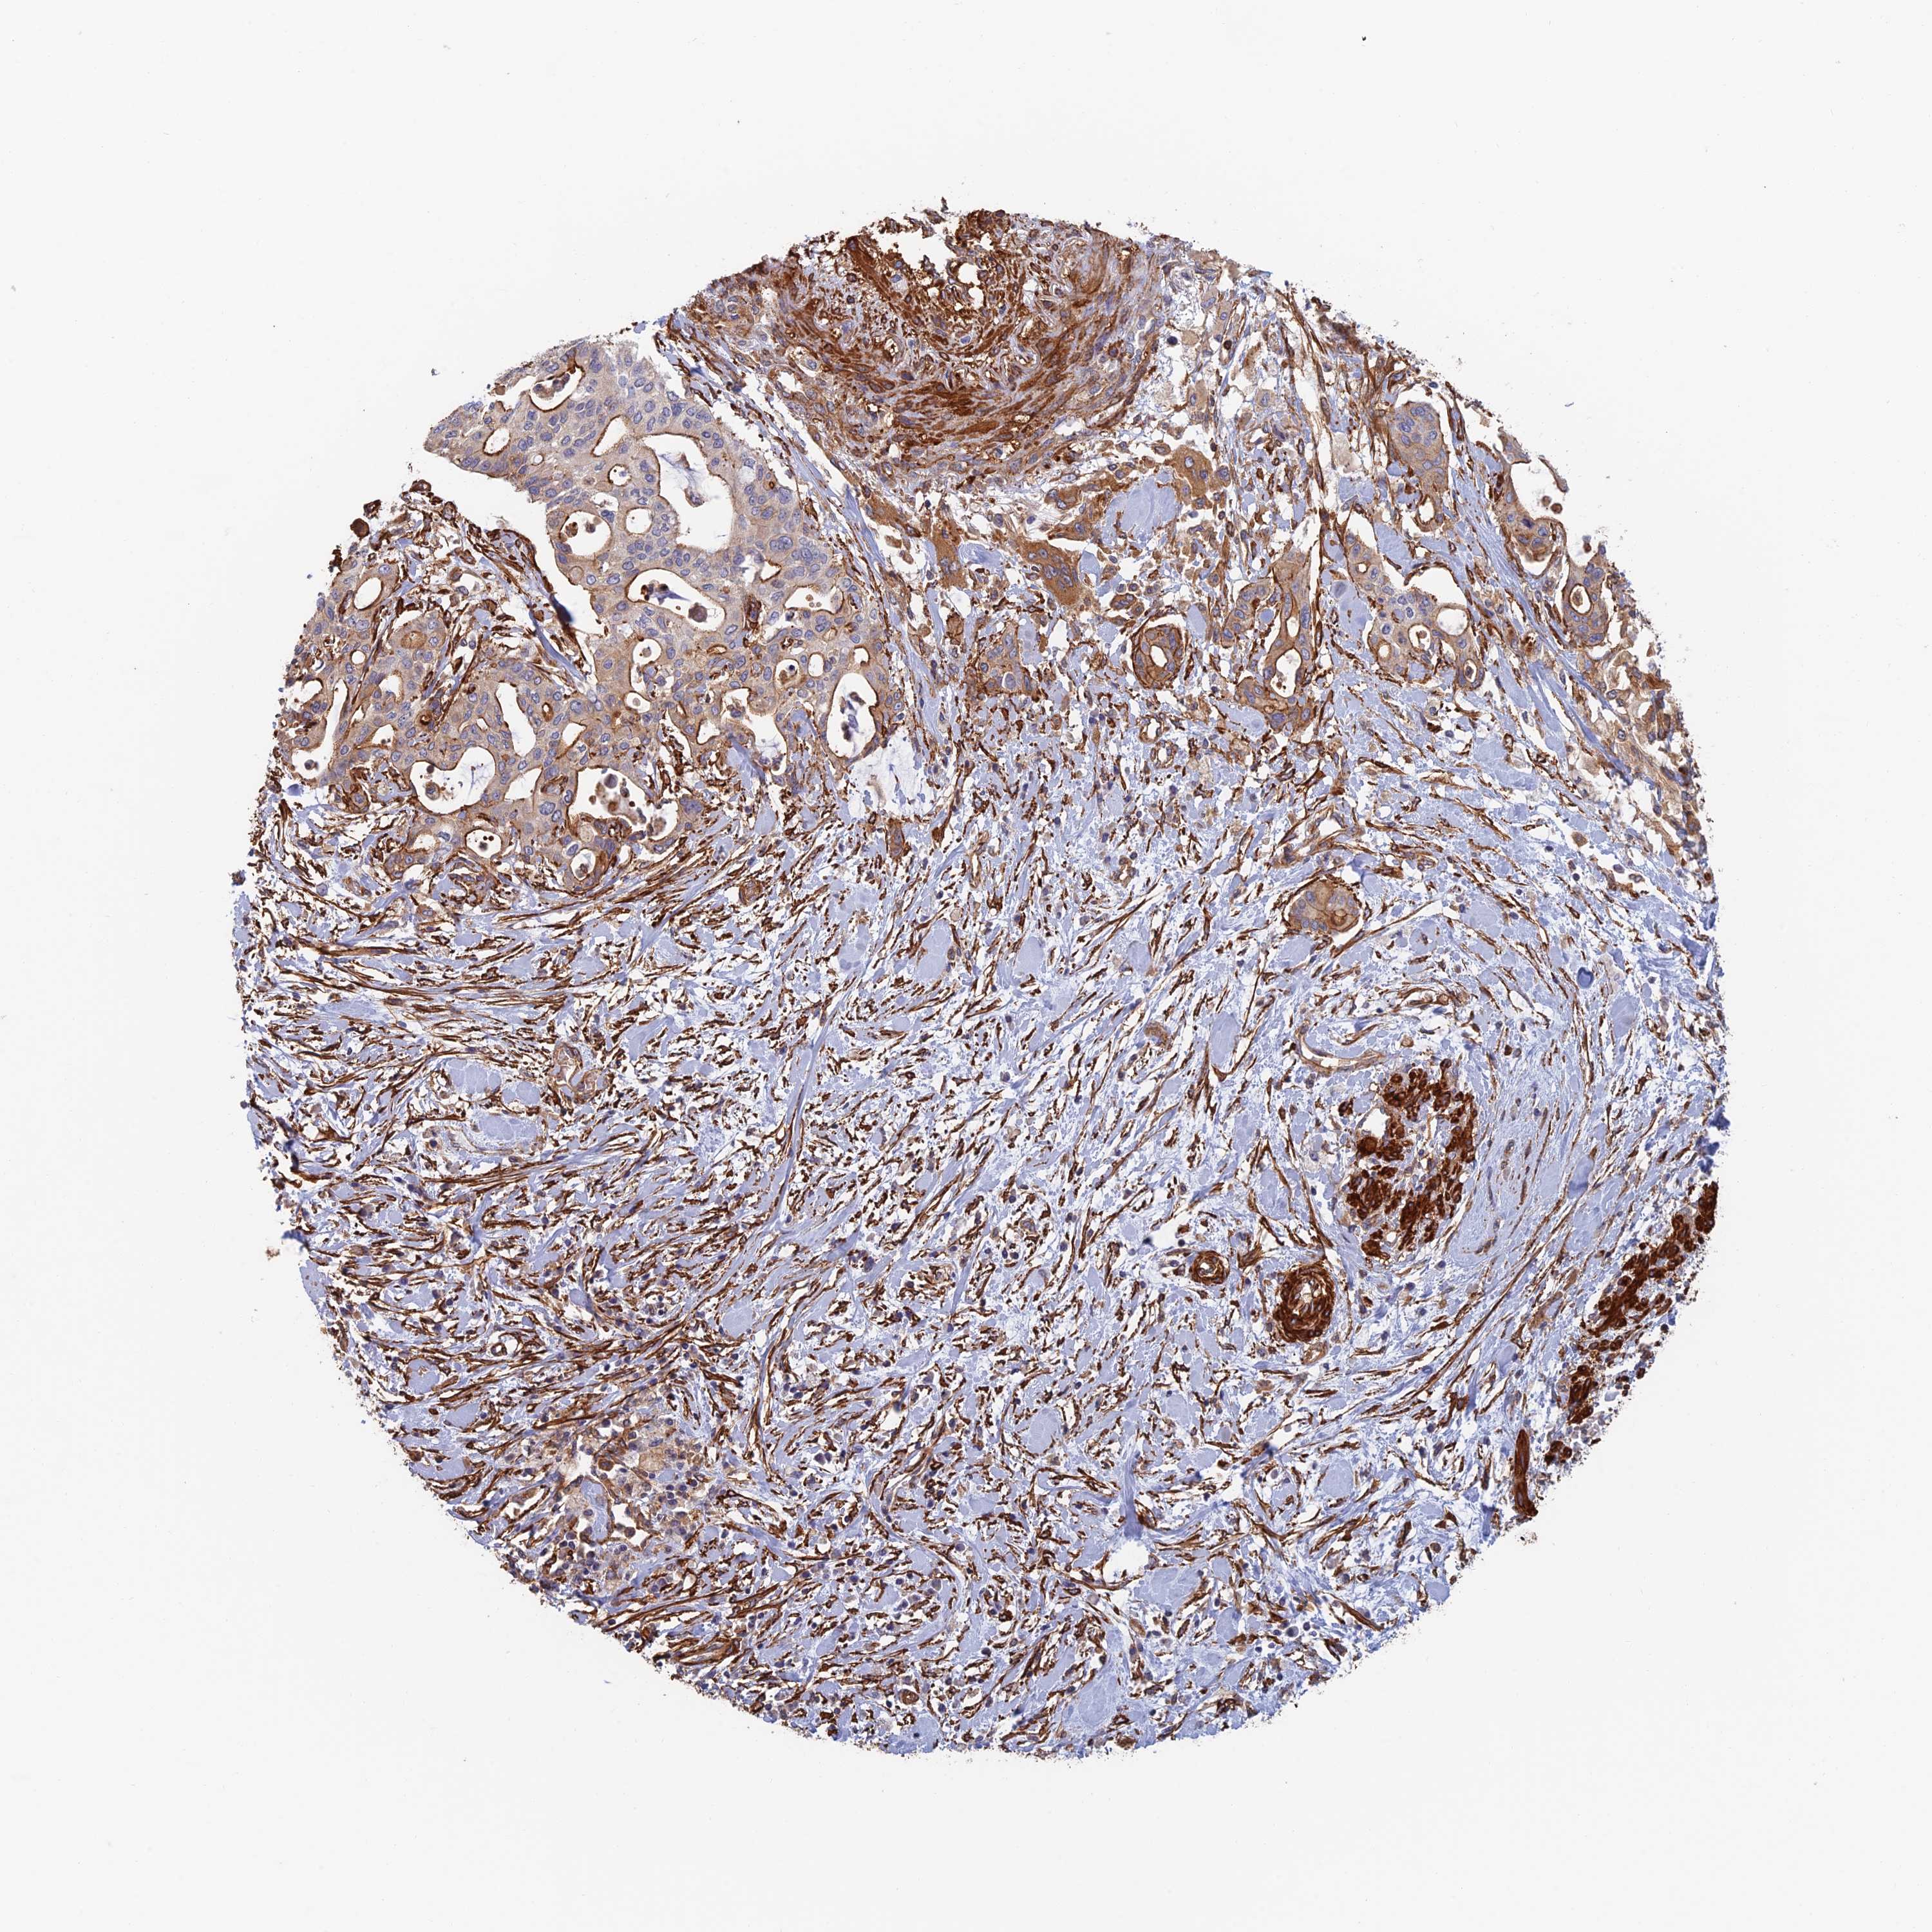

PANCREATIC CANCER - Protein expressioni

A mouse-over function shows sample information and annotation data. Click on an image to view it in a full screen mode. Samples can be filtered based on level of antibody staining by selecting one or several of the following categories: high, medium, low and not detected. The assay and annotation is described here.

Note that samples used for immunohistochemistry by the Human Protein Atlas do not correspond to samples in the TCGA dataset.

Antibody stainingi

Antibody staining in the annotated cell types in the current human tissue is reported as not detected, low, medium, or high, based on conventional immunohistochemistry profiling in selected tissues. This score is based on the combination of the staining intensity and fraction of stained cells.

Each image is clickable and will lead to virtual microscopy that enables deeper exploration of all samples and also displays staining intensity scores, fraction scores and subcellular localization as well as patient and tissue information for each sample.

Antibody CAB025747

Antibody CAB044670

Staining

High

Medium

Low

Not detected

Intensity

Strong

Moderate

Weak

Negative

Quantity

>75%

75%-25%

<25%

None

Location

Nuclear

Cytoplasmic/membranous

Cytoplasmic/membranous,nuclear

Adenocarcinoma, NOS

Adenocarcinoma, metastatic, NOS